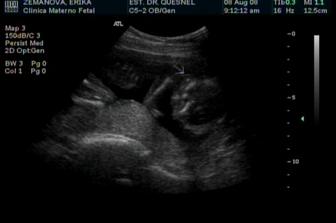

8.8.2008 - Tak si představte, co se dneska stalo! Zase mě vzali k tomu pandoktorovi. To by ještě nebylo tak nejhorší, člověk si nakonec zvykne na všechno, i když je teprve malá píďalka. Jenomže! Před tím do mě asi půl hodiny pořád něčím šťouchali a koukali na mě v televizi! No hrůza! Jak já se styděl... snažil jsem se zalézt někam do koutka, ale nakonec mě stejně všude objevili. A měřili mě snad od hlavy až k patě. To jsem si přece nemohl nechat líbit, a tak jsem sebou aspoň mrskal co to šlo, aby si mysleli, že mám místo jedné hlavičky dvě. No, neskočili mi na to... a navíc, jako pomstu, mi ještě okukovali tu bouličku... no... tu... jak mi tuhle narostla mezi nožičkama. Fakt nevím, co je na tom mohlo tak zajímat, osobně netuším, k čemu by to mohlo být dobré - snad tak leda na hraní... Pámbuvíproč, mamka se u toho smála, až jí tekly slzy. A víte co? Má u mě schovaných pěkných pár kopanců za to, že mi přestala říkat Píďalka. A já už si na to celkem zvyknul... Tak čau zase někdy.